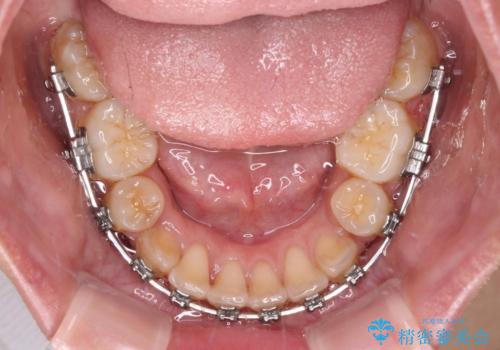

- メタルブラケット

- 3年3ヶ月

- 30回以上

奥歯の噛み合わせは正常に近い状態でしたが、右上の奥歯に突起があったり、上下前歯が非接触であったりしていたため、補助装置を使用して上顎前歯を積極的に引っ込めるように計画しました。

口元の突出感を改善するために上下左右の小臼歯4本を抜歯し、ワイヤー装置によりデコボコを解消しながら口元の突出感も改善していくこととしました。